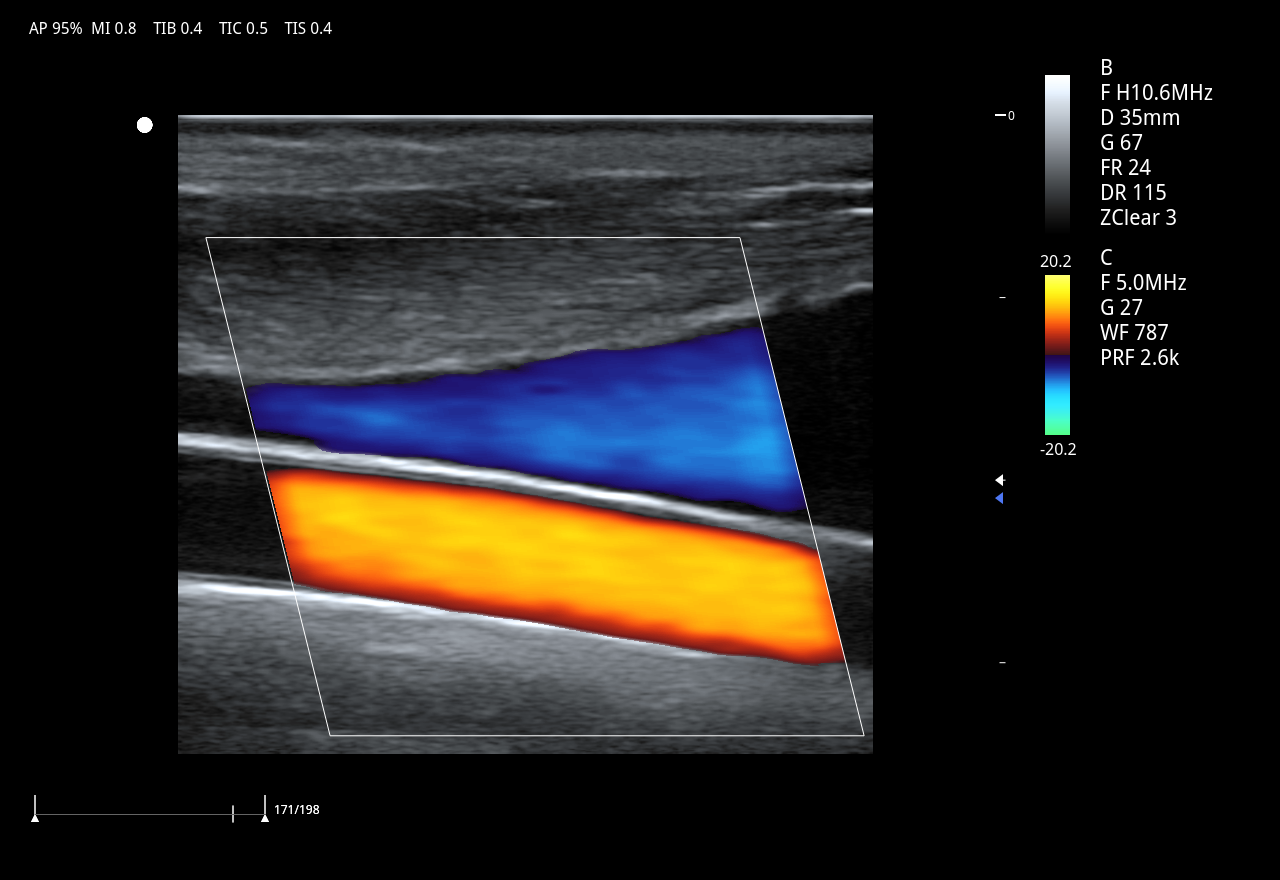

Color Doppler (CDFI), Power Doppler (PDI/DPDI)

HR Flow y zMicroFlow para microvasculatura

Imágenes clínicas extraordinarias